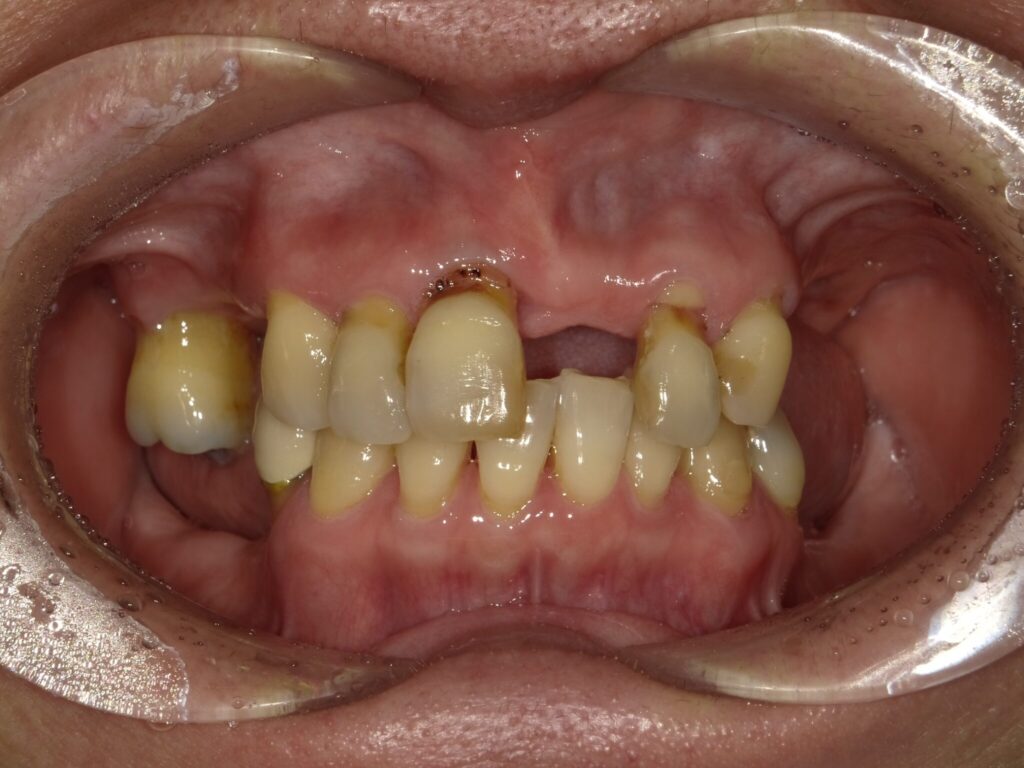

インプラント埋入(右上4・6,左上4・6,右下6,左下6) ジルコニアBr(右上3―左上3) ジルコニア(右下5,左下5) …続きを見る